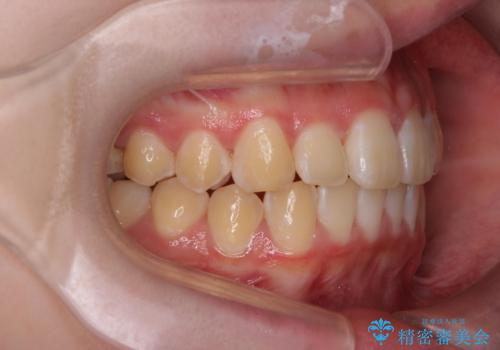

前歯のがたつき気になる。インビザラインモデレート

- 前歯のがたつきが気になるとの事で来院。

マウスピース矯正希望でしたのでインビザラインモデレートで治療を行いました。

がたつきが無くなり満足して頂けました。